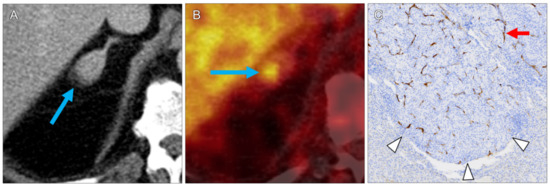

| 7 | right humerus | 8.1 | 15.2 | 23.4 | 13.7 | 26.0 | 3 | ccRCC | 3 | 2 | 4 | 3 |